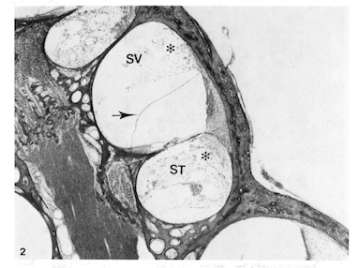

Middle turn of cochlea of the chinchilla 12 hours following endotoxin instillation

(A) Middle turn of cochlea of the chinchilla 12 hours following endotoxin instillation. Inflammatory cell infiltration and bleeding (*) are seen in perilymphatic spaces and spiral ligament with mild endolymphatic hydrops (arrow). SV: scala vestibuli, ST: scala tympani.